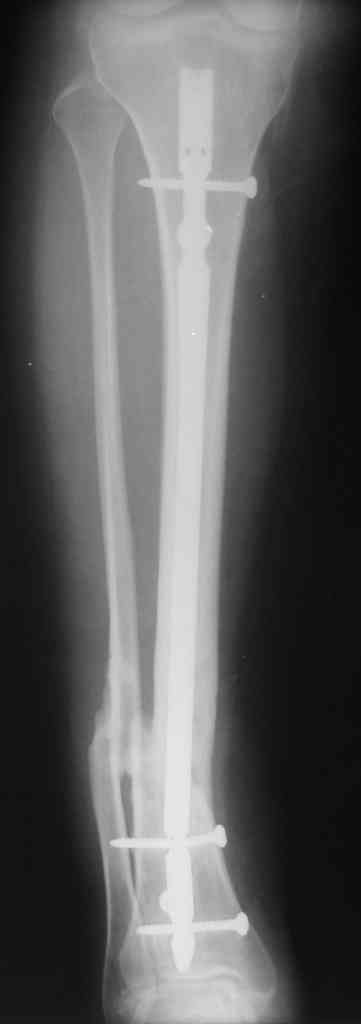

[Ortho] Ложный сустав голени перелом штифта

Р-граммы по теме прилагаю

Имя     : Г.jpg